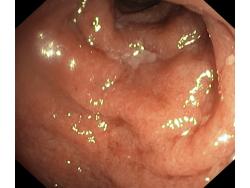

Zapalenie wrzodziejące jelita grubego